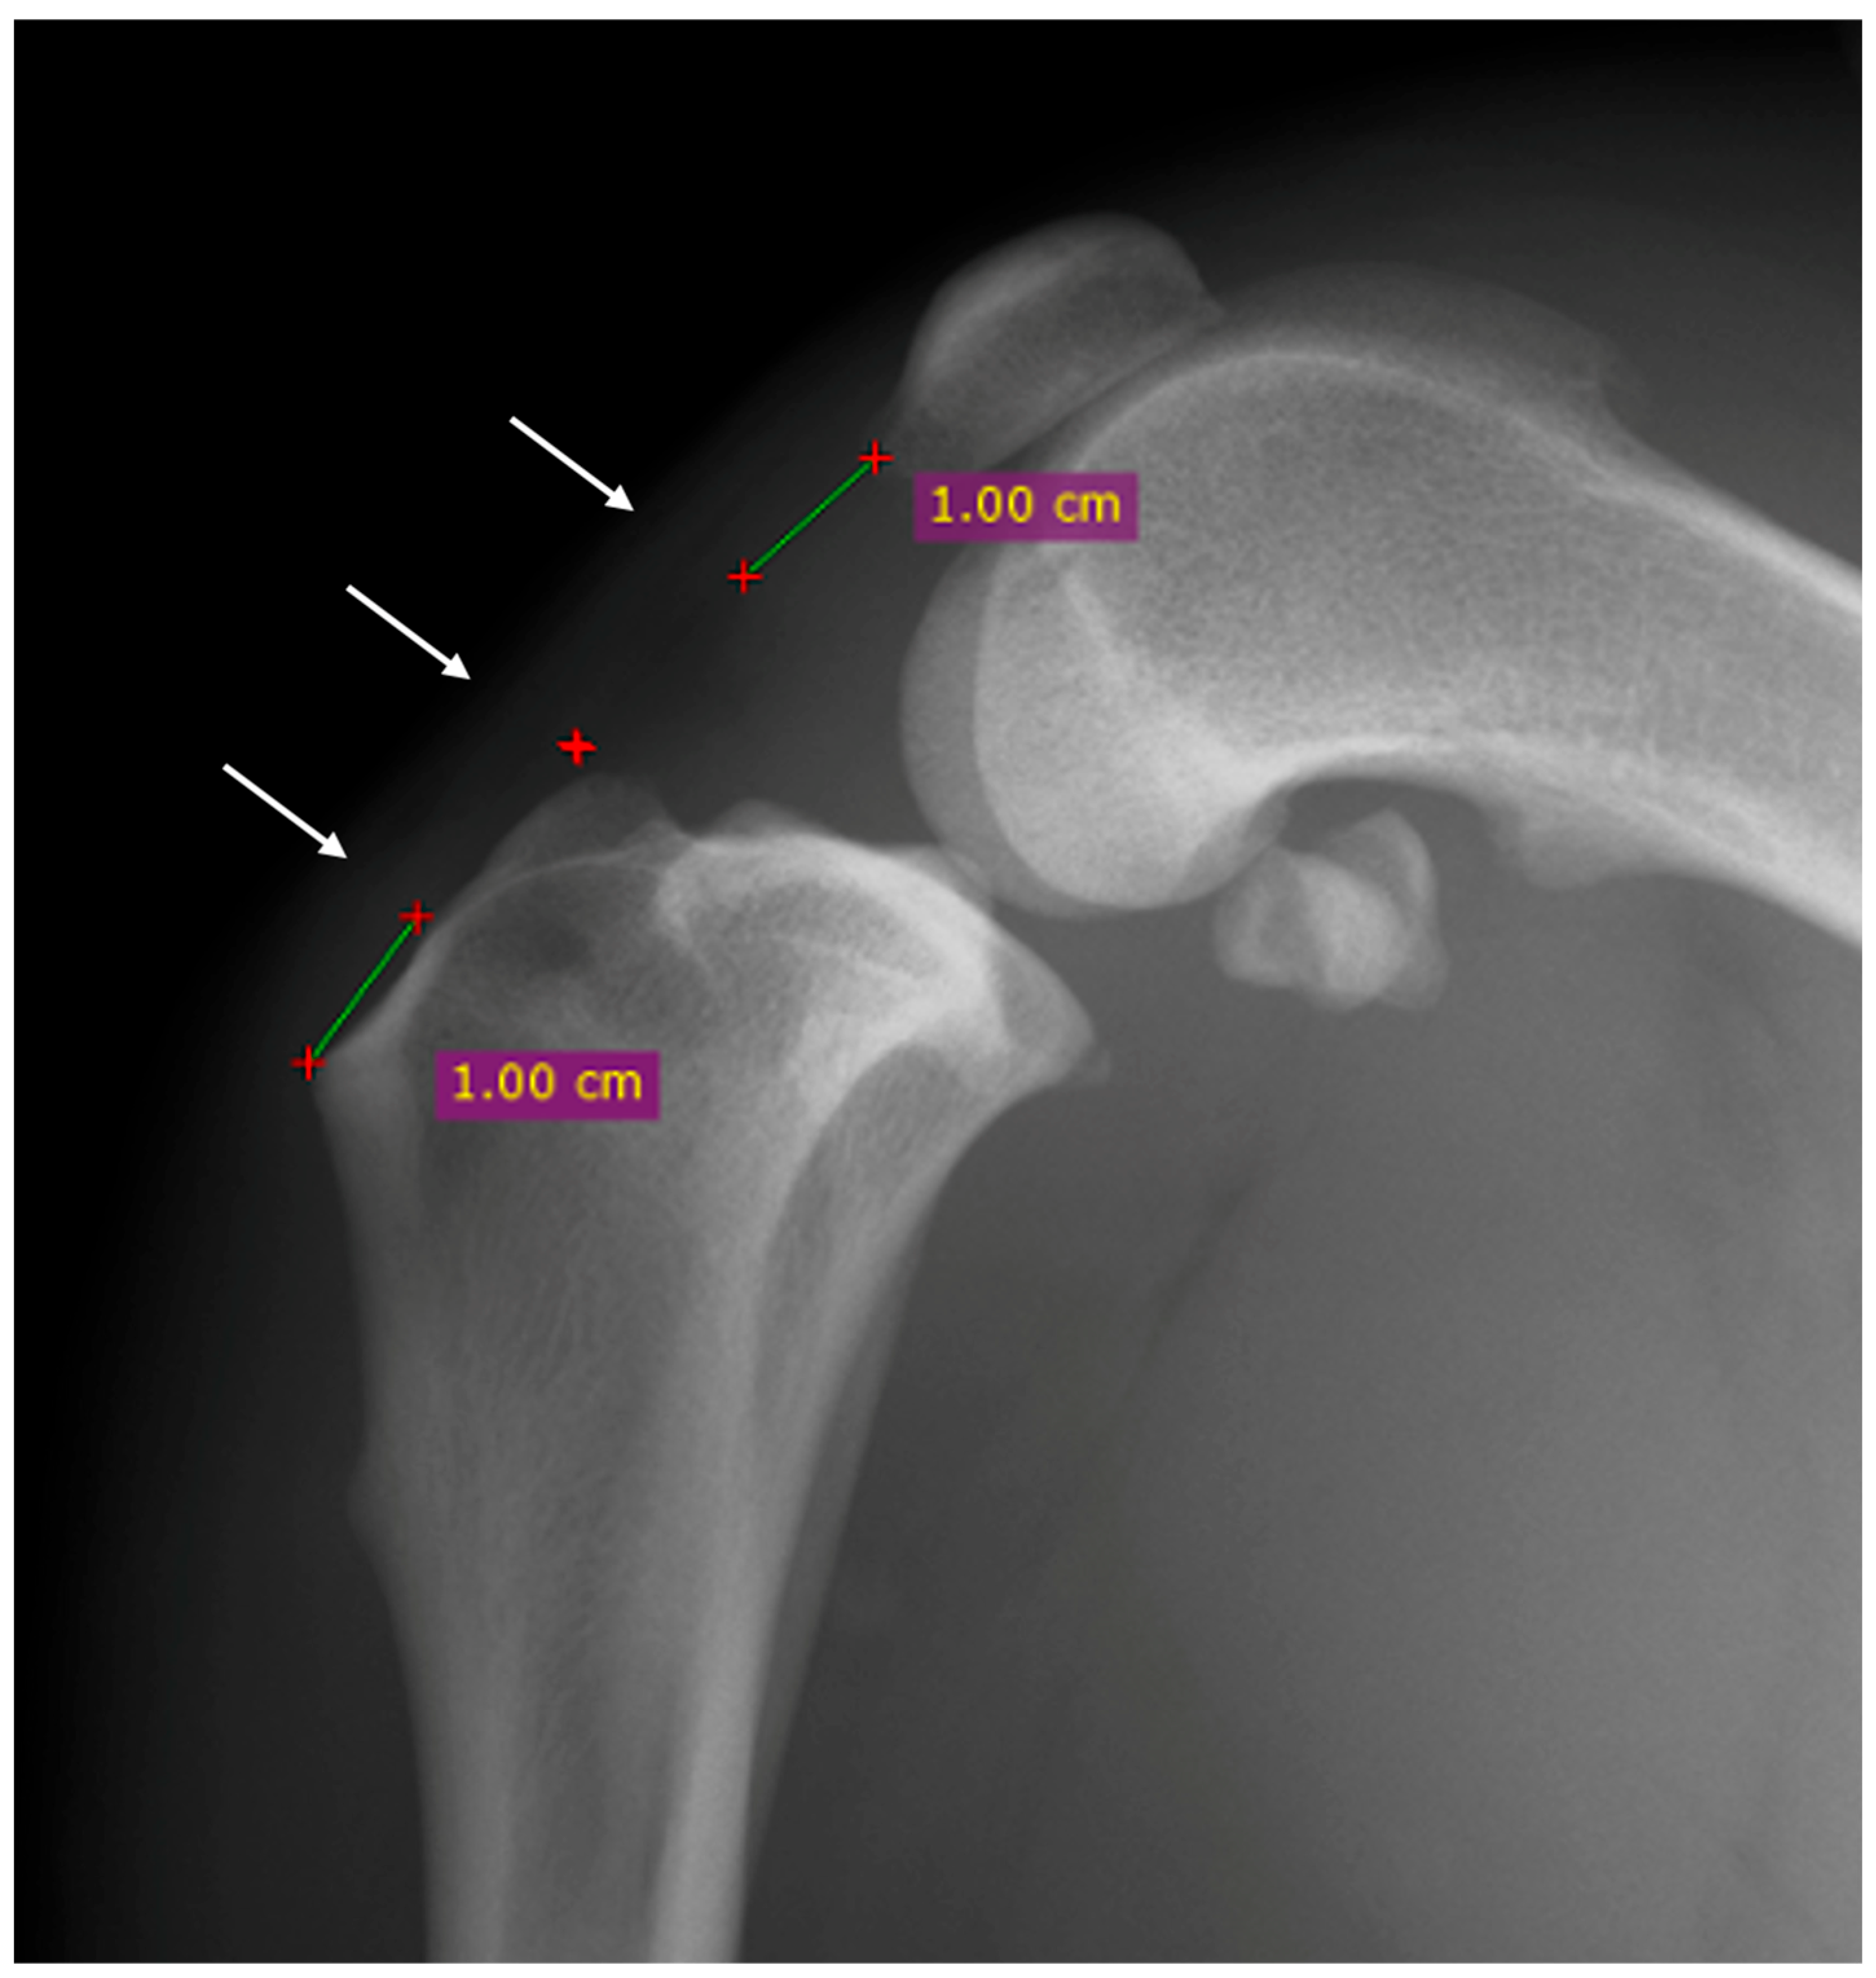

The proximal point was established one centimeter distally to the base of the patella, the distal point was established one centimeter proximally to the tibial tuberosity, and the central point was halfway between the first two points previously described (Figure 1) [16].

Mediolateral radiographic view of the stifle before the surgery. The thickness of the patellar was evaluated at three points: proximal, central and distal (white arrows). The proximal point was established one centimeter distally to the base of the patella (green line), the distal point was established one centimeter proximally to the tibial tuberosity (green line) and the central point was halfway between the first two points previously described (red cross).